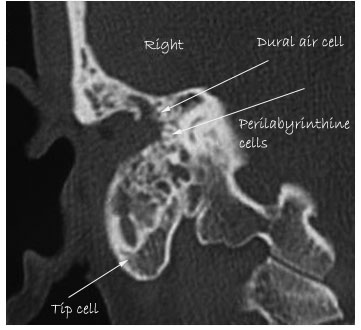

HRCT image of temporal bone showing pneumatization

3. Perilabyrinthine: Supralabyrinthine and infralabyrinthine

Temporal bone pneumatization can be best studied by High resolution CT scan. This procedure shows clearly the complete pneumatization with excellent resolution.